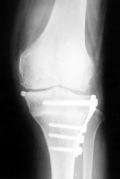

この手術法には、外側クローズド楔形骨切り術、ドーム型骨切り術、片側オープン楔形骨切り術、斜位脛骨近位骨切り術、などの方法があります。この内、一般的に行われてきたのが前2者です。ドーム型骨切り術は創外固定という、骨に金属の棒を骨切り部の上下に刺入し、固定する方法で、棒が皮膚から出ているため入浴など出来ず、現在あまり行われなくなりました。外側クローズド楔形骨切り術はよく行われ、その固定材料は多く製品化されてきました。Blade plate、Giebel plate、Natural knee plate、Interlocking stapleなど有名です。1990年代にNatural knee plate systemが登場すると、手術の正確性とやりやすさから脛骨骨切り術は比較的簡単な方法として行われるようになりました。しかし、欠点として腓骨の骨を1-2cm程度切除しなくてはなりません。

Natural knee plate